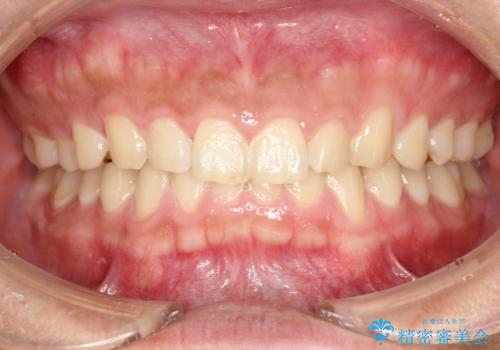

- 半年ぶりの来院で、全体的なチェックとクリーニング希望でした。PMTC(自費クリーニング)60分コースを行いました。

PMTCとは、プロフェッショナル(歯科衛生士)メカニカル(機械的)トゥース(歯)クリーニング(清掃)の略です。歯科医院にて、いろいろな機械・材料を使用し汚れを落とします。

磨き残しや、細菌は歯の表面がザラザラしている部分につきやすいです。そのためPMTCを定期的に繰り返すことで、歯の表面がツルツルの状態である期間が長くなるため、虫歯や歯周病予防につながります。